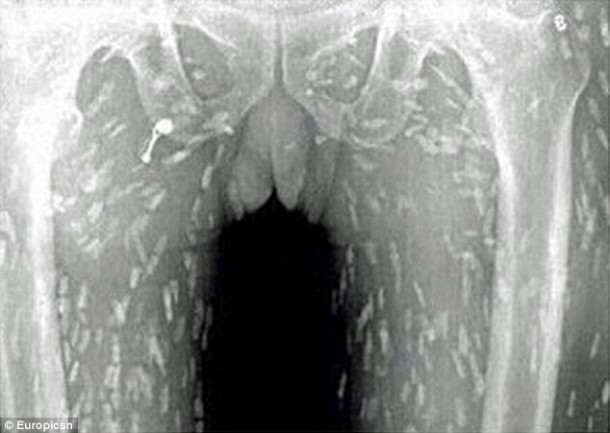

Sur place, le médecin lui fait passer des radiographies pour identifier la cause de son mal-être. Les radiographies révèlent que l’homme a des larves de ténia dans tout le corps. Le Dr Yin, a indiqué que l’homme « avait probablement mangé du poisson cru contaminé par des oeufs ». C’est à cela que l’homme doit son infection parasitaire. Si son cas n’avait pas été traité rapidement, l’homme aurait pu mourir. En effet, lorsque l’infection atteint le cerveau, cela peut se révéler mortel.